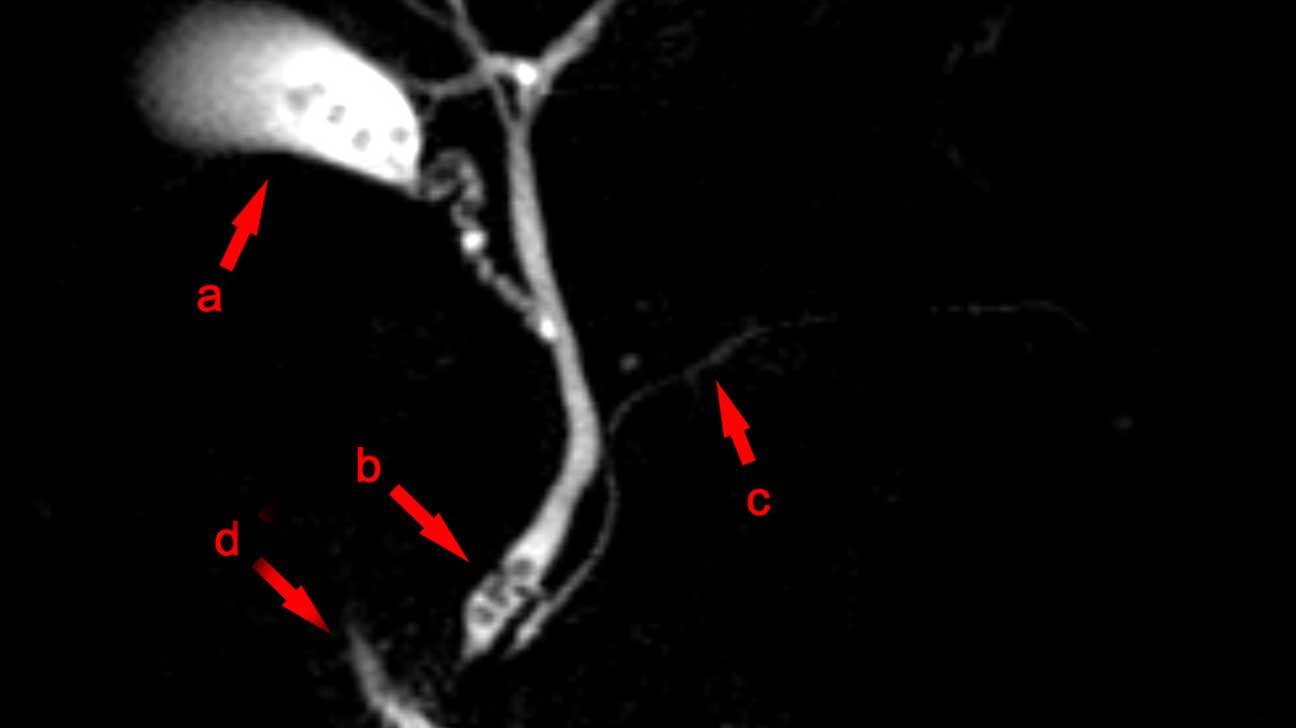

膽管(膽管)阻塞(Biliary (bile duct) obstruction)

這種情況被認為是醫療緊急情況。可能需要緊急護理。

最常見的是由膽結石引起,但也可能是由肝臟或膽囊損傷,炎症,腫瘤,感染,囊腫或肝臟損傷引起的

皮膚或眼睛發黃,皮膚極度搔癢,無皮疹,淺色大便,尿液很暗

腹部右上方疼痛,噁心,嘔吐,發燒

阻塞可導致嚴重感染,需要緊急醫療護理